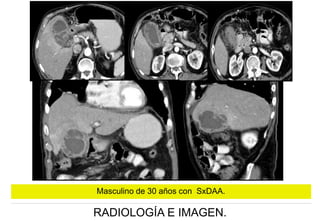

Masculino de 30 años con SxDAA.

QUIRÚRGICO:

PERFORACIÓN VESICULAR

CONTENIDA POR EPIPLON

PIOCOLECISTO

LITIASIS VESICULAR

COLECISTITIS AGUDA

GANGRENADA

COLECISTITIS CRÓNICA